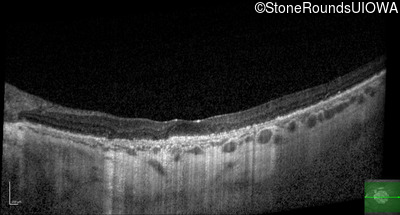

Optical Coherence Tomography - Left - 5/400

Exemplar / OCT Stack